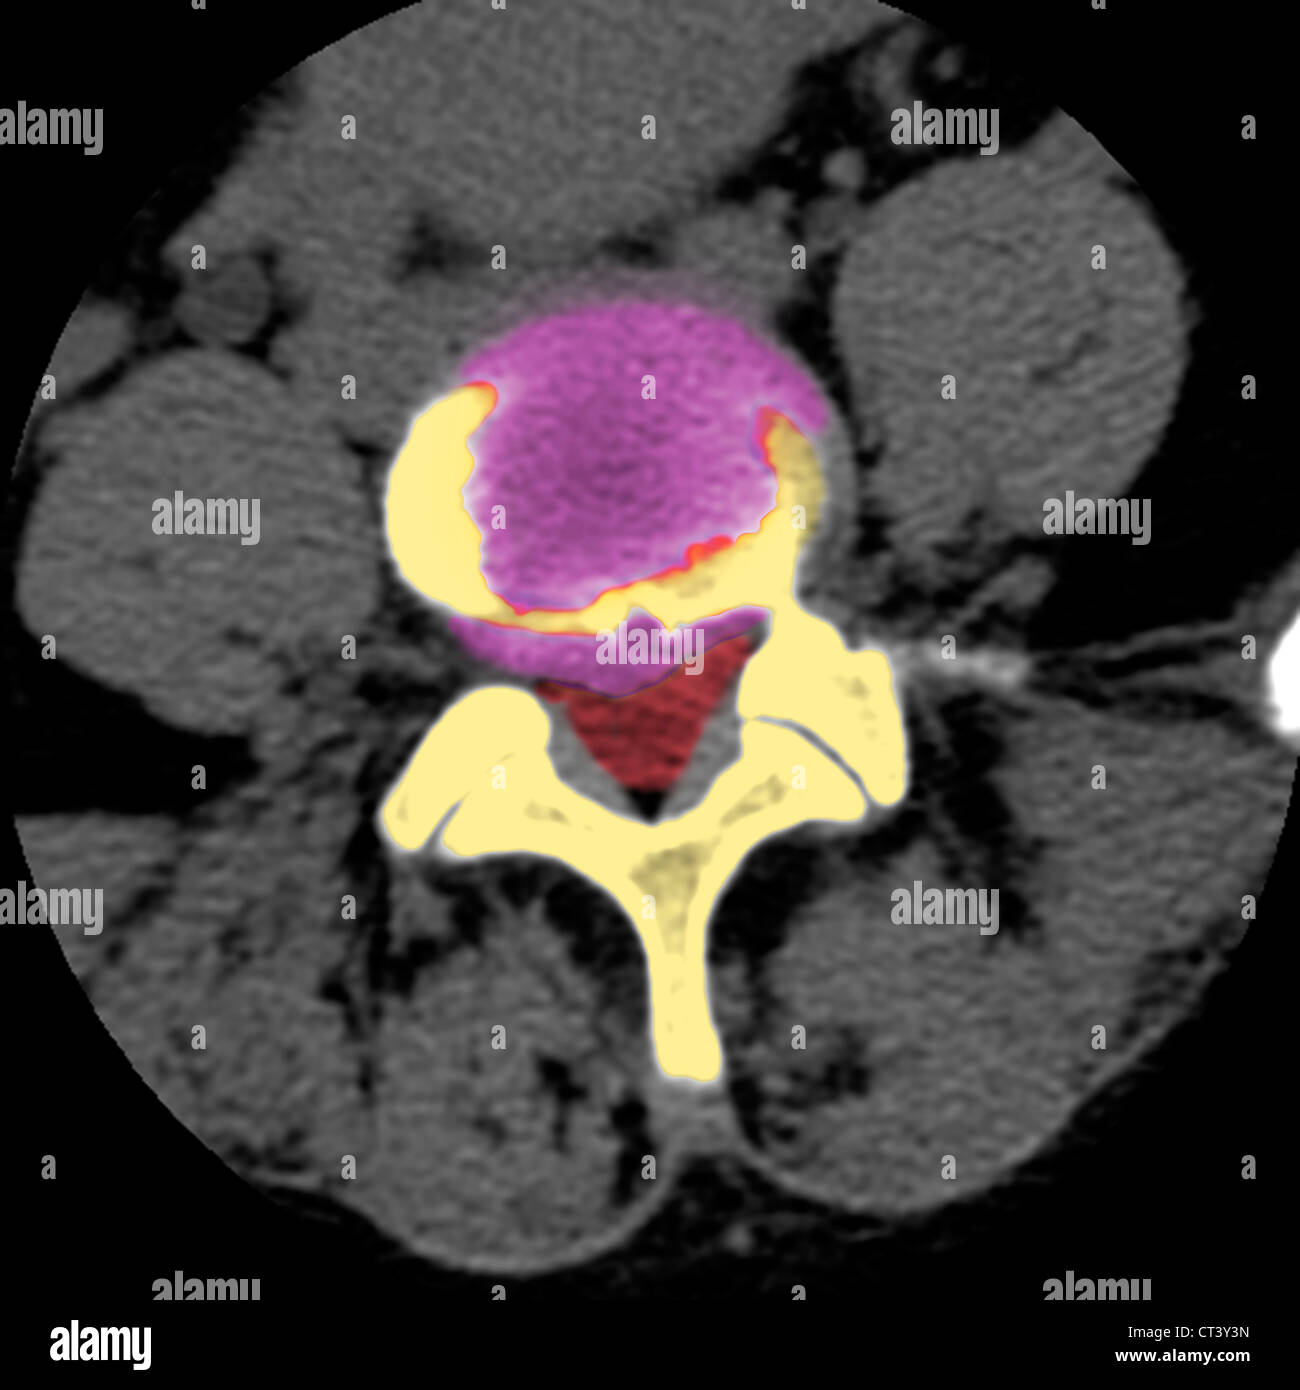

From pixels.com

Disc Herniation, Ct Myelogram Photograph by Living Art Enterprises Pixels Herniated Disk X Ray The most common and accurate imaging test for a suspected herniated disk is an mri. See images of disc herniation, facet arthrosis, synovial cysts and other causes of nerve root. Medical history, physical exam, and advanced imaging tests. Learn how to diagnose nerve compression in the lumbar region with mri. Learn about the three steps involved in diagnosing a lumbar. Herniated Disk X Ray.

From www.sciencephoto.com

Herniated disc, CT scan Stock Image C048/7476 Science Photo Library Herniated Disk X Ray Learn about the three steps involved in diagnosing a lumbar herniated disc: A herniated disk occurs when the soft center of a spinal disk slips out of its casing and can press on nearby nerves. Disc herniation is the displacement of disc material beyond the normal confines of the disc, involving less than 25% of the. See images of disc. Herniated Disk X Ray.